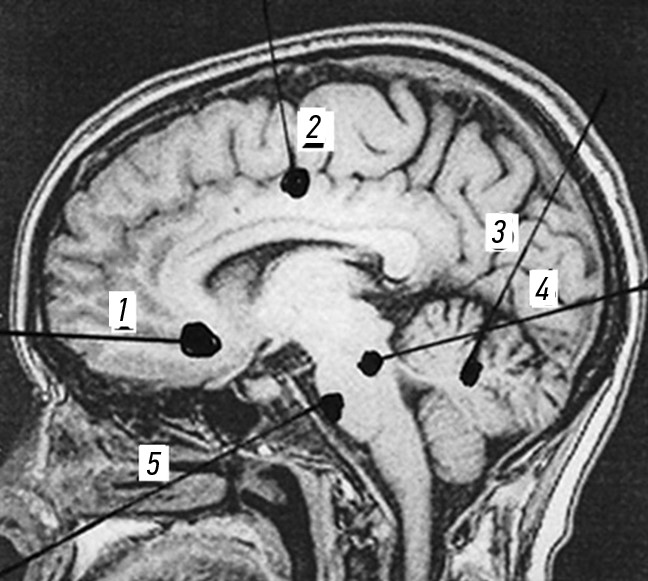

Ходы раневых каналов при огнестрельных проникающих осколочных ранениях черепа и ГМ, также примеры диагнозов продемонстрированы на рис. 3–7.

Рис. 5. Огнестрельные проникающие диаметральные ранения черепа и головного мозга. Примеры диагнозов: 1 — минно-взрывное ранение (МВР). Огнестрельное осколочное слепое (сквозное) проникающее диаметральное ранение лобных долей головного мозга; 2 — МВР. Огнестрельное осколочное слепое (сквозное) проникающее диаметральное ранение левой лобной и правой теменной долей головного мозга; 3 — МВР. Огнестрельное осколочное слепое (сквозное) проникающее диаметральное ранение левой теменной и правой лобной долей головного мозга; 4 — МВР. Огнестрельное осколочное слепое (сквозное) проникающее диаметральное парамедианное ранение правой лобной, теменной и затылочной долей головного мозга; 5 — МВР. Огнестрельное осколочное сквозное проникающее незавершенное диаметральное ранение правой теменной и левой лобной долей головного мозга.